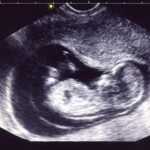

3人の子育て真っ最中です世の中には素晴らしい育児法や育児書が沢山あります実際に効果があったオススメの方法や、逆効果になってしまう様な方法子供によっては選別しなくてはいけません試行錯誤して得た体験談等を書いて行きます